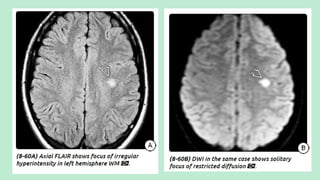

MR findings (depends on time since

ictus and hemorrhagic transformation):

1.T1WI: Non hemorrhagic infarct shows

hypointensity with moderate mass effect and

sulcal effacement. However, the hemorrhagic

transformation shows the iso signal intensity

with cortex initially followed by

hyperintensity.

2.T2WI: Initially hyperintense, with time the

signal intensity decreases reaching iso at the

one to two weeks known as “T2 fogging

effect”.

These infarcts shows hyperintesity on FLAIR images. Final infarct volume

corresponds to FLAIR defined abnormality after one week.

T2* gradient echo images show the hemorrhagic transformation as petechial

or gyriform blooming foci. However in basal ganglia it can be petechial or

confluent.

DWI shows hyperintensity with hypointensity on ADC map for first

several days,which then gradually reverse subsequently.

T1 contrast images shows intravascular enhancement in first 48 hrs which is

replaced by leptomemingeal enhacement caused by persisting pial collateral

blood flow after three to four days. Patchy and gyriform enhancement occurs

as early as two to three days and may persist for two to three months.